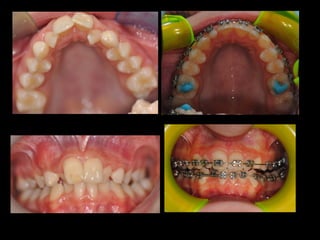

Posterior Crossbite in the mixed dentition is a

common malocclusion, with a prevalence that

varies from 4% to 23%

Phatouros A, Goonewardene MS Morphologic changes of the

palate after rapid maxillary expansion: a 3-dimensional

computed tomography evaluation Am J

OrthodDentofacialOrthop. 2008 Jul;134(1):117-24

Physiological

condition

Posterior

bilateral

unilateral

crossbite

Clinically the relevance of the topic is clear,

since transverse occlusal discrepancies are

relatively common, with uni or bilateral

crossbites, occurring in 9.4 per cent of boys

and 14.1 per cent of girls (Helm, 1968).

The transverse dimension represents the sum

of the skeletal maxillary base and the

inclination of the buccal segment teeth and

surrounding alveolar bone (Solow, 1980).

Discrepancies involving the skeletal base

should be treated by skeletal expansion,

whereas dentoalveolar discrepancies should

be corrected by tooth movement.

Clinically transverse contraction of the

jaws occurs with posterior crossbite

MONOLATERAL BILATERAL

158

In the skeletal discrepancy in the transverse

dimension of the jaws and denture bases, mostly we

use

RAPID PALATAL EXPANSION

Haas AJ. Long-term posttreatment evaluation of

rapid palatal expansion. Angle Orthod.1980 Jul;

CENTRAL

SCREW

skeletal increase in the lateral

dimension of the nasal cavity and

maxillary bone after palatal disjunction

Chung C, Font B. Skeletal and dental changes in the sagittal, vertical and

transverse dimensions after rapid palatal expansion.Am J Orthod

Dentofacial Orthop. 2004;126:569-75.

Hershey HG, Stewart BL,Warren DW. Changes in nasal airway resistance

associated with rapid maxillary expansion.Am J Orthod Dentofacial Orthop.

1976;69:274-84.

As a result,we will have a

transverse improvement of

the occlusion and a nasal

expansion

In literature we don’t find real guidelines that

tell us what is the best choice in various clinical

situations

In our Dental School we are researching if

could exist real advantages using permanent or

deciduous teeth as anchorage, evaluating the

amount of expansion obtained

What are the best anchor teeth?

In literature is possible to find cases of adverse effects

on anchor teeth:

!Exostosis

!Pulp stones

!Root resorption

!Gingival recessions

Timms DJ, Moss JP. An

histological investigation into

the effects of rapid maxillary

expansion on the teeth and

their supporting tissues.

Trans Eur Orthod Soc.

1971:263-71

To avoid iatrogenic damage to the permanent teeth, it’s

possible to use deciduous as anchor teeth

Garib DG, Henriques JF, Janson G, de Freitas MR, Fernandes

AY. Periodontal effects of rapid maxillary expansion with

tooth-tissue-borne and tooth-borne expanders: a computed

tomography evaluation. Am J Orthod Dentofacial Orthop.

So we can choose

OR

First permanent

molars used as

anchor teeth

Second deciduous